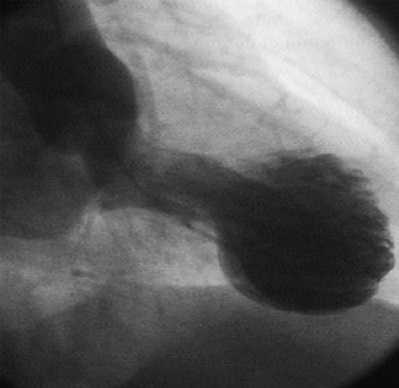

Кардиомиопатия такоцубо имеет множество синонимов: синдром «разбитого сердца» (СРС), стресс-индуцированная кардиомиопатия, синдром верхушечного баллонирования. Необычное название «такоцубо» происходит от японского слова tako-tsubo, что в переводе означает «ловушка для осьминога». Это приспособление имеет широкое основание и узкое горлышко — похожую форму приобретает левый желудочек во время приступа. Кардиомиопатия такоцубо выявляется у 1-2% пациентов с острым коронарным синдромом. Более 90% больных — женщины в постменопаузальном периоде.

- Коронарная ангиография. Назначение исследования в ургентном порядке целесообразно для исключения инфаркта миокарда. При кардиомиопатии такоцубо визуализируются неизмененные коронарные сосуды с сохраненным кровотоком. Для уточнения диагноза рекомендована левожелудочковая вентрикулография.

Термин «такоцубо» (tako-tsubo) в переводе с японского языка означает приспособление для ловли осьминогов - керамический горшок с круглым основанием и узким горлышком. Именно такую форму у больных при эхокардиографии приобретает левый желудочек (ЛЖ) в систолу, что объясняется отсутствием сокращения его верхушки с одновременным избыточным сокращением базальных отделов [4].

Наиболее специфичные изменения при ЭХО-кг и контрастной вентрикулографии. Характерен акинез или дискинез верхушки и средней части ЛЖ с гиперконтрактильностью основания и обструкцией выходного тракта ЛЖ. При этом форма ЛЖ напоминает приспособление для ловли осьминогов. Общая систолическая функция снижается, а средняя ФВ ЛЖ варьируется в диапазоне от 20 до 49 процентов [1, 2, 31].

Ангиография является ценным методом диагностики. Принципиальное отличие кардиомиопатии токацубо от острого коронарного синдрома - отсутствие гемодинамически значимого стеноза коронарных артерий.